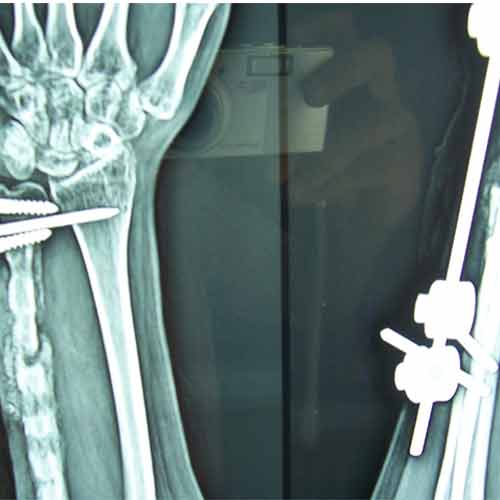

Case:13 Infected nonunion with implant failure

31 years old patient with fracture radius-ulna (1-year-old) with infected non-union was treated with implant removal & external fixation. ‘K’ wiring was done for distal radio-ulna joint stabilization. Bone grafting was done after 3 weeks. Fracture united 6 months’ post-operative.

Pre-Op

Post-op

Imm Post-op

Bone gratfing + ex fix

6 months post-op